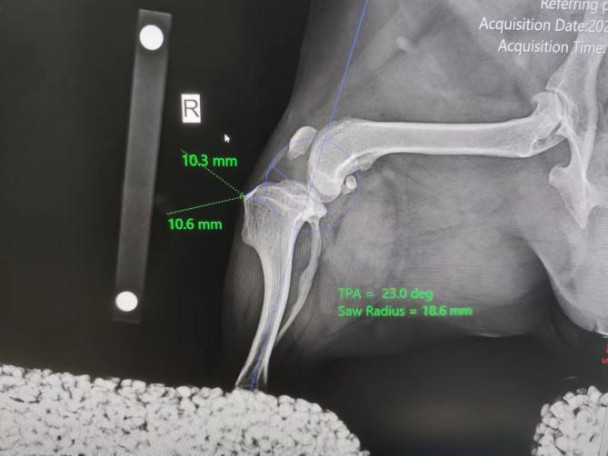

Short-acting anesthesia was administered with intravenous propofol at a dose of 8mg / kg. Put an indwelling needle, prepare endotracheal intubation to start anesthesia, and take bilateral knee position and open side. The X-ray showed a ruptured JOJO anterior cruciate ligament, positive drawer motion on palpation, movement of the popliteal fascia, and mild arthritis. No abnormalities were noted in the left hind limb.

Pet X-ray inspection pictures